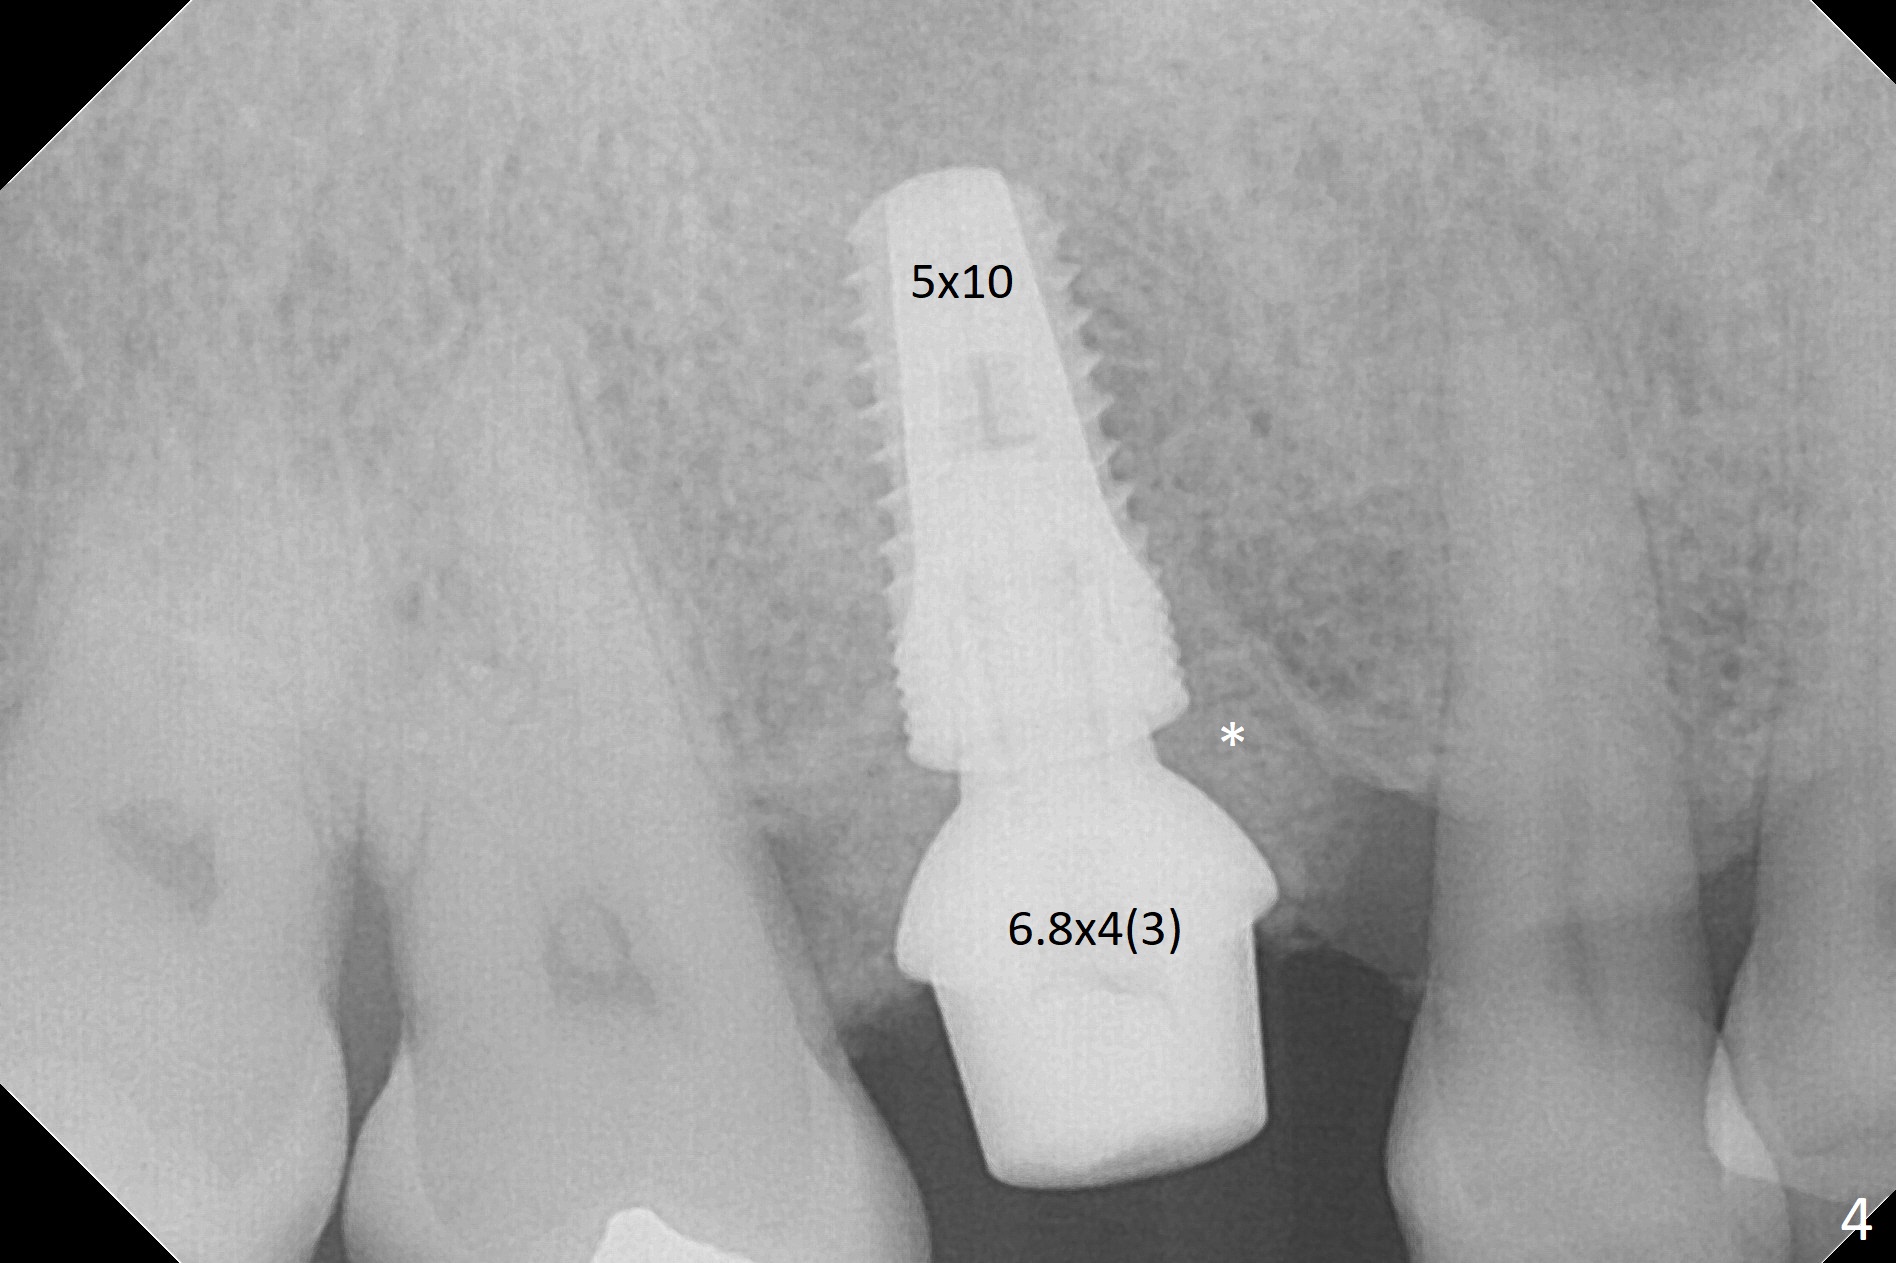

Short Implant Placed Deep

The clearance between the residual roots of the tooth #3 and the abutment at #30 seems to be somewhat limited (Fig.1). The initial osteotomy depth is 10 mm (Fig.2). After moving the osteotomy mesially, the depth increases to 12 mm; a parallel pin is inserted for 16 mm (Fig.3 with sinus membrane perforation). The depth of the rest of the osteotomy is 10 mm with placement of a 5x10 mm implant with >50 Ncm (Fig.4); with insertion of a 6.8x4(3) mm abutment and Vera Graft (*), an immediate provisional is fabricated. Collagen plug is used to seal the gap between the provisional and the gingiva. The abutment dislodges nearly 1 month postop; the wound has healed (Fig.5). A 8.2x5(4) mm healing abutment is placed to keep the soft tissue configurement.